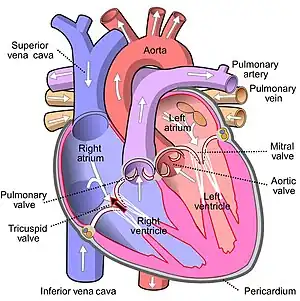

| Diagram of the heart with a black arrow showing the location and direction of the abnormal blood flow | |

Tricuspid insufficiency (TI), also known as tricuspid regurgitation (TR), is a type of valvular heart disease in which there is backward flow of blood from the right ventricle, through the tricuspid valve, into the right atrium, when the heart contracts.[1] Early on few symptoms may be present.[1] Later on heart failure may develop with peripheral swelling, liver enlargement, and ascites.[1] Other complications may include atrial fibrillation.[1]